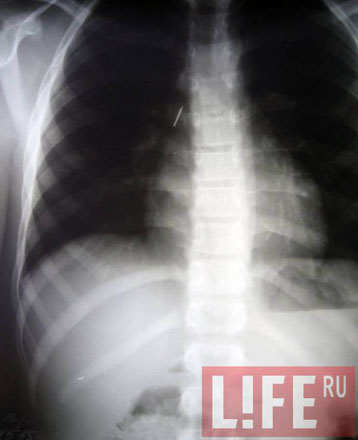

На рентгене врачи ясно увидели металлическое острие в бронхах ребенка.

- Медлить было нельзя, - рассказал анестезиолог-реаниматолог Максим Анохин. - Кровотечение могло открыться в любую минуту.